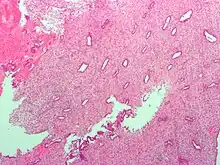

![]() Endometrium in the proliferative phase | |

The endometrium consists of a single layer of columnar epithelium plus the stroma on which it rests. The stroma is a layer of connective tissue that varies in thickness according to hormonal influences. In the uterus, simple tubular glands reach from the endometrial surface through to the base of the stroma, which also carries a rich blood supply provided by the spiral arteries. In women of reproductive age, two layers of endometrium can be distinguished. These two layers occur only in the endometrium lining the cavity of the uterus, and not in the lining of the fallopian tubes.[4][5]

It is possible to identify the phase of the menstrual cycle by reference to either the ovarian cycle or the uterine cycle by observing microscopic differences at each phase—for example in the ovarian cycle:

| Phase | Days | Thickness | Epithelium |

| Menstrual phase | 1–5 | Thin | Absent |

| Follicular phase | 5–14 | Intermediate | Columnar |

| Luteal phase | 15–27 | Thick | Columnar. Also visible are arcuate vessels of uterus |

| Ischemic phase | 27–28 | Columnar. Also visible are arcuate vessels of uterus |